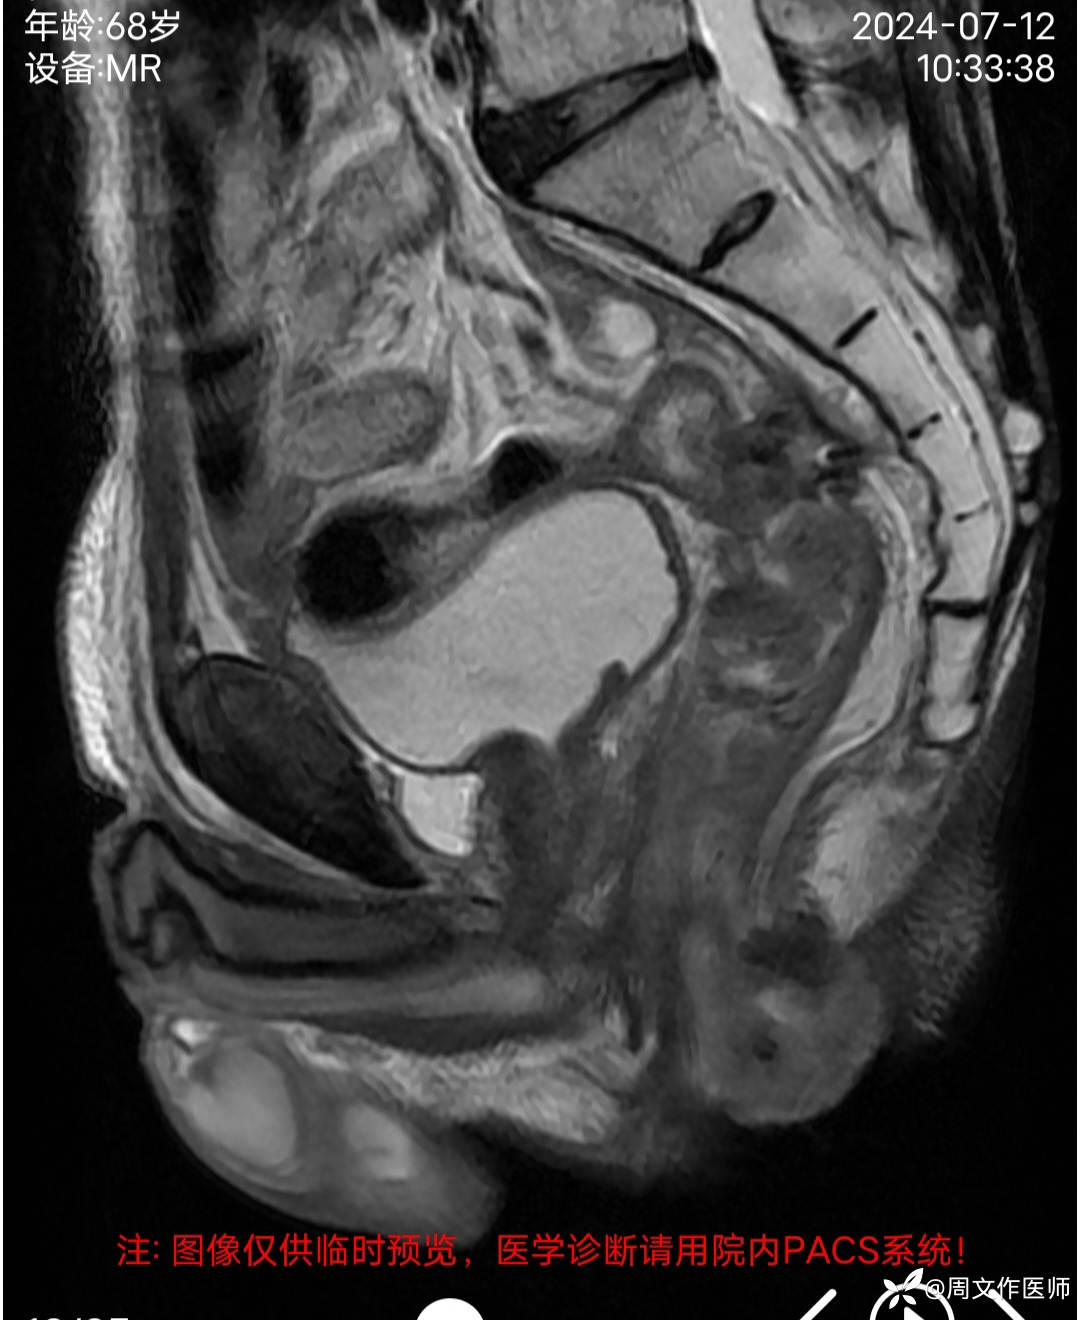

患者男性,68岁,主诉:发现肛门肿物伴出血4年余,加重1月。

现病史:患者诉4年前发现肛门肿物,无疼痛等不适,未引起重视,2年前出现疼痛、出血,脓血溢出至我科住院治疗,完善相关检查确诊直肠癌并发多器官转移至肿瘤科化疗14次,2024年3月因直肠癌肿坏疽穿孔并弥漫性腹膜炎、肠梗阻在外院行 Hartmann手术;病情好转后出院,1月前感肛门肿物逐渐增大,出血及疼痛加重。今日到我院就诊,门诊以"1.肛门肿物;2.便血"收住入院。目前症见:肛门肿物突起,伴疼痛、出血,偶有脓血溢出。病程中患者精神、纳眠稍差,二便正常。体重下降5公斤。

MRI检查